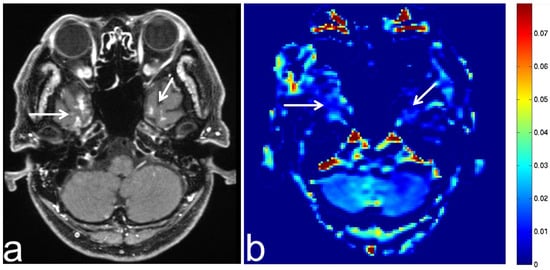

7.3. Schwannoma